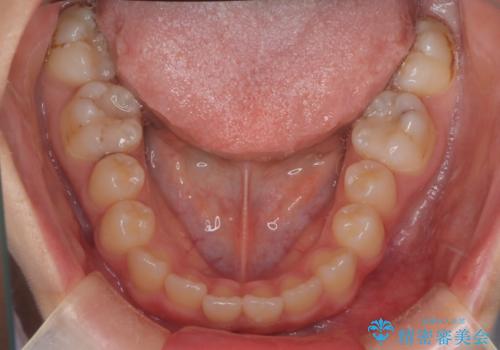

マウスピース矯正で前歯のガタツキを改善! 短期間で治療完了

- 前歯のガタツキが気になるとのことで来院されました。

前歯のガタツキに加え、奥歯の噛み合わせにも問題があったため、マウスピース矯正で治療し改善しました。